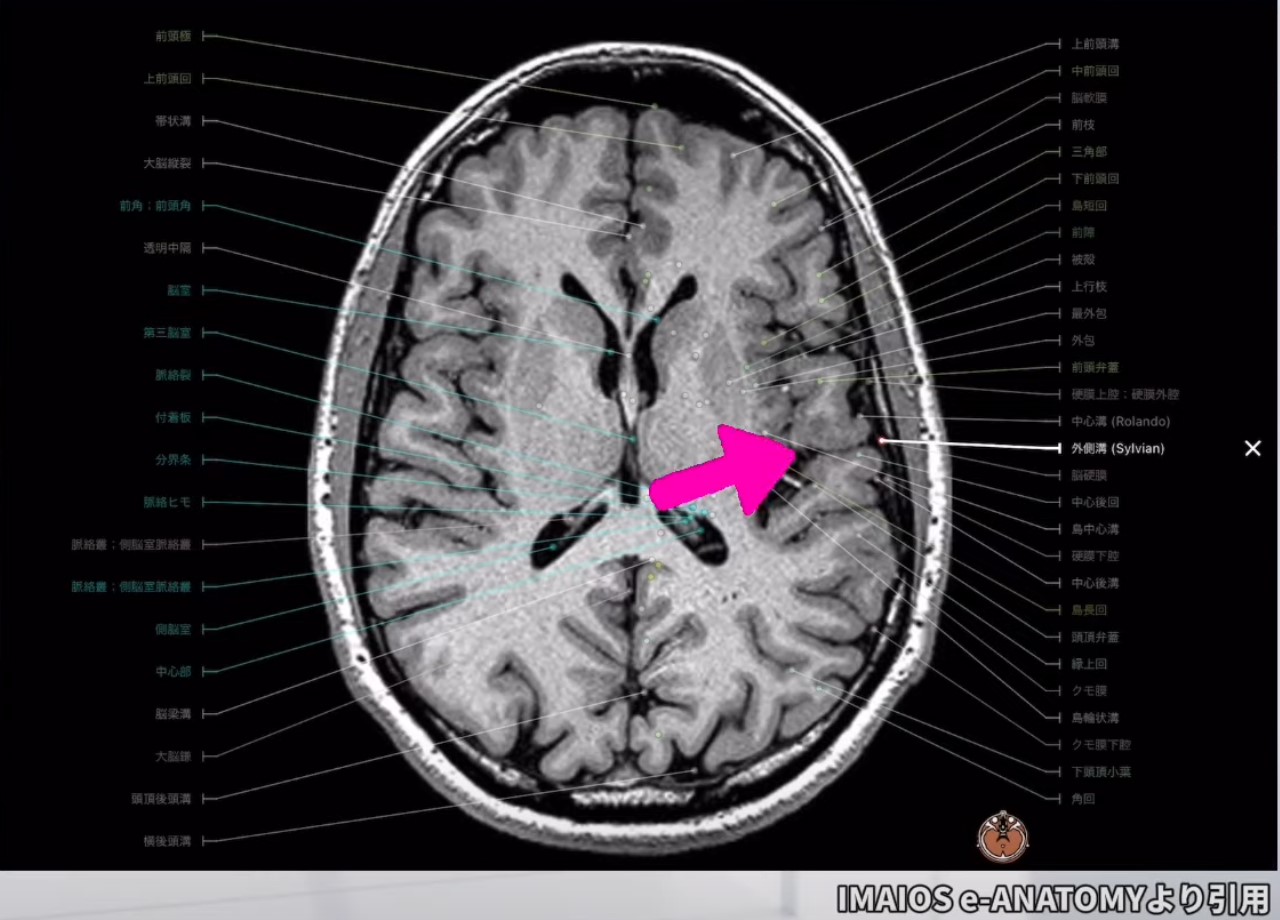

出発点としてのシルビウス裂

基本的なランドマークとしてのシルビウス裂

- シルビウス裂(外側溝)は脳の外側面に位置する深い溝であり、側頭葉と前頭葉・頭頂葉を分ける重要なランドマークです。

- MTGを特定する際の出発点として、まずシルビウス裂を明確に識別します。

シルビウス裂からの位置関係

- シルビウス裂から下方に進むと、最初に上側頭回(STG)が現れ、そのすぐ下に中側頭回(MTG)が位置します。

- シルビウス裂はMTGの上方境界を決める間接的な指標となります。

- シルビウス裂との関係: シルビウス裂はMTGの上方境界として認識できます。